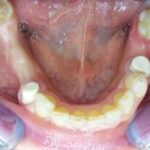

Patientenfall, zahnloser Unterkiefer. Komplett metallfreie Lösung. Der Zirkonium-Steg auf 4 Implantaten garantiert einen absolut festen Sitz, Sicherheit und Kaukomfort.

4 Implantate im Kinnbereich

Ein Zirkoniumsteg zur Befestigung des Zahnersatzes

Steg auf dem Modell

Unterkiefertotalprothese auf PEEK-Gerüst

Prothese von unten